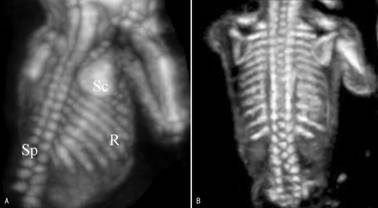

三、脊柱冠状切面

不同水平的冠状面显示的图像差异很大。胸腰部冠状面扫查可显示典型的脊柱冠状面图像,在近腹侧经椎体的冠状切面上显示为串珠状强回声。超声检查无法在一个平面上显示自然屈曲的脊柱冠状切回声,位于图像中央区域的椎体比较大,向边缘区域椎体逐渐变小;可显示中间的椎体回声和双侧的椎弓回声所形成的三条带状回声,显示双侧椎弓时仅可见由双侧椎弓形成的带状回声,中央的椎体骨化中心不显示。

上述脊柱冠状面图像在脊柱的三维超声检查时显示的更为典型,并通过三维图像可以比较明确的计数椎体的数目(图2A),并且可以在胸部显示肋骨回声和数目(图2B)。

图2 胎儿脊柱(SP)和肋骨(R)三维显示